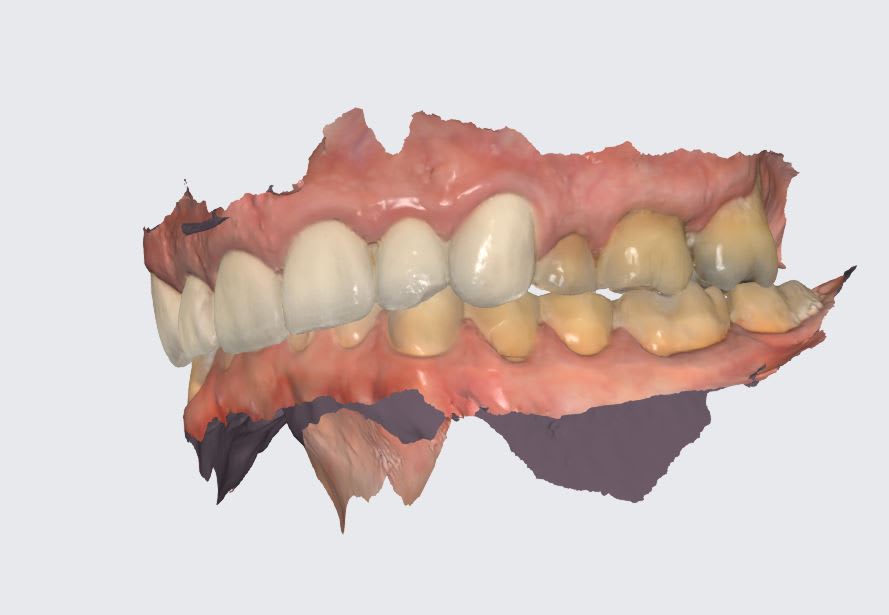

Bon, américain de 70 ans, ressemble à Castex, donc la bombasse j'ai pas sous la main, usure étrange à 60° maxillaire palatine sur les molaires. Vient 15 jours, a pas les moyens de se faire traiter aux USA, ne demande pas la lune mais de pouvoir mâcher des burger sans avoir mal. je me demande si une restauration postérieure peut faire l'affaire, suis tellement étonné de la forme de l'usure des mol maxillaires.

Wakrap , ton Américain a un sur guidage ant avec en plus un sur-contact cingulaire en fin de mvt de fermeture .

ce qui fait qu il se retrouve avec une oim en arrière de sa centrée , à tous les coups .

si tu veux reconstruire derrière , il faut lui donner de l espace devant , donc refaire le bloc ant , puisque je vois que tu es déjà sur le métal .

quand tu es comprimé des atm , il faut que tu te trouves du jeux pour te détendre un petit peu , et ce jeux , il l a trouvé en fracassant les molaires ce qui lui permet d avoir une liberté droite gauche .

en gros le jeux antero post qu il a perdu , il l a compensé en se créant un jeux latéral .

Parce que ça n’y ressemble pas ici tout simplement. T’as déjà tout résumé: classe 2, bloqué par la palissade de CCM antérieur, effondrement de la DVO évidente.

Les attaques acides laissent systématiquement des traces jaunes-orangés sur les tissus dentaires. Les 7 seraient plus atteintes que les 6, et il y aurait une attaque en lingual des inf. Ici le bas est bouffé en vestibulaire et le haut en palatin, leur usure est mécanique: effondrement DVO chez CL2 qu’on a enfermé en antérieur. Voir aussi si on a pas une langue en position reculée et une tendance au SAHOS…..,mais pas régurgitation acide:vomissements,

25,26 et 27 sont niquées de la même façon en palatin. Et la perte de substance va jusqu'en sous gingival. Si c'était mécanique, il se boufferait aussi la gencive.